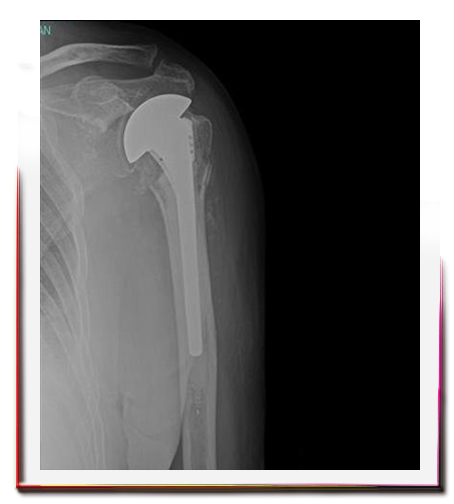

Omuz kırığında protez ameliyatı ne zaman gerekir?

Bazen yaralanma, kırık parçalarına, tespiti mümkün olamayacak kadar fazla zarar verir. Çok parçalı kırıklı çıkıklar, parçaların tespit edilemeyecek kadar ince ve osteoprotik olduğu durumlarda hastanın yaşam kalitesinin arttırılması ve ağrısının sona erdirilmesi amacıyla protez cerrahisi kullanılabilir.